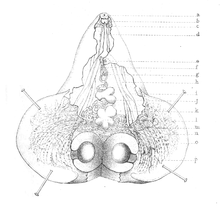

| Longitudinal section of an adult | |

It is a large fluke, somehow vase-shaped and bright-pink in colour. In average it measures 5–8 mm long and 3–5 mm wide. The disc-shaped body is divisible into anterior conical and posterior discoidal regions. The anterior region is a conical projection bearing a prominent oral sucker. The posterior portion is relatively broad (up to 8 mm), discoidal and ventrally excavated. It is an amphistome worm such that the ventral sucker is close to the posterior end.[11] The body covering, tegument is smooth in appearance but the fine structure is actually a series of concentric folds bearing numerous tightly packed tubercles. Ventral surface contains a specialised region of the tegument. Ciliated and non-ciliated papillae are arranged around the oral sucker.[12][13] The incomplete alimentary canal consists of a pair of lateral pouches arising from the oral sucker and a slightly tortuous pharyngeal tube, which bifurcates into two gut caeca. The large excretory bladder is in the middle behind the ventral sucker. As a hermaphrodite, both male and female reproductive system are present which are arranged in the posterior region. The testes lie in alongside the bifurcation of the caeca, and a common genital pore is on the cone just anterior to the bifurcation. The oval-shaped ovary lies just posterior to the testes in the middle, and the loosely coiled uterus opens to the genital pore. Vitelline glands are scattered around the caeca.[8]